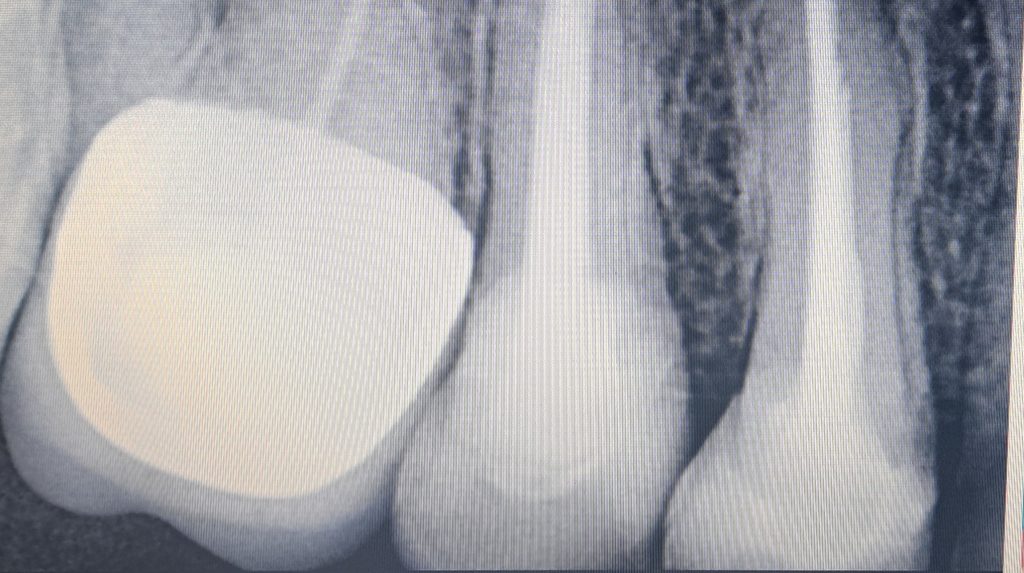

I decided to go for indirect lithium disilicate restorations

And final design to receive to monolithic lithium disilicate restorations